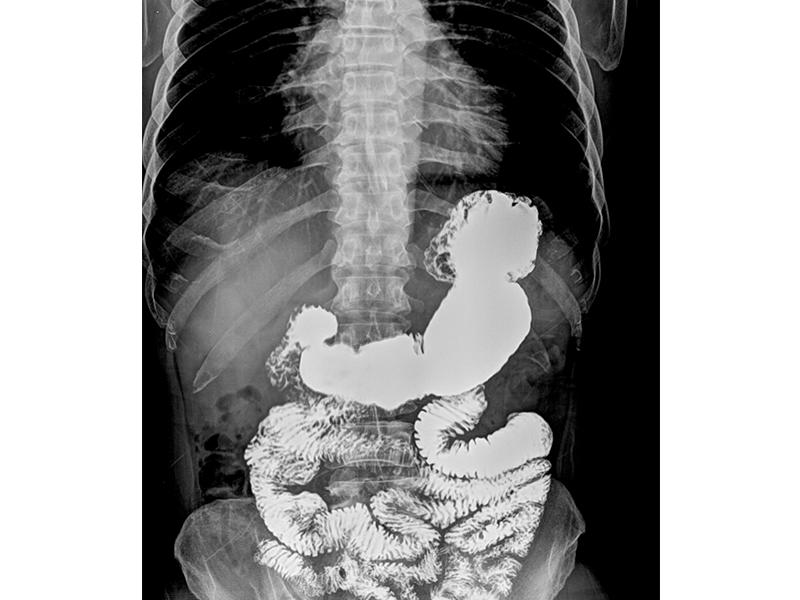

الانسداد المعوي Intestinal Obstruction أسبابه وعلاجه وأعراضه